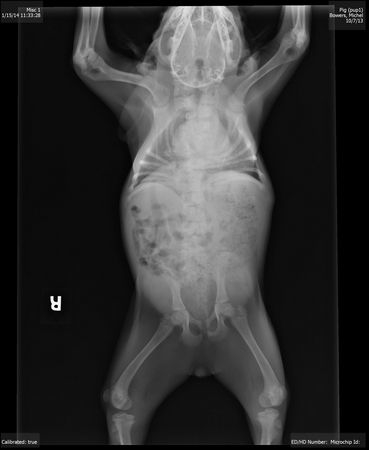

У Хрюши неполный набор спинных позвонков, одна часть позвонков отсутствует, другие из них срослись, а третьи были перекручены вместе со спинным мозгом

Также у Хрюши отсутствует пара ребер и суставы её бедер вывернуты в неправильной форме

У неё большие проблемы с тем участком спинного мозга, который находится ближе к шее